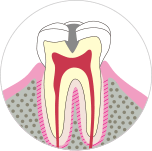

段階.C1

エナメル質が細菌におかされ小さな黒い穴があきます。

エナメル質には神経がないので痛みなどはなく、自覚症状がありません。定期的な検査を行うことで発見は可能です。

主な症状

- ・小さな黒い穴があく

- ・歯の表面に艶がなくなる

- ・薄い茶褐色になる

治療法

- ・つめもの(CR:樹脂)